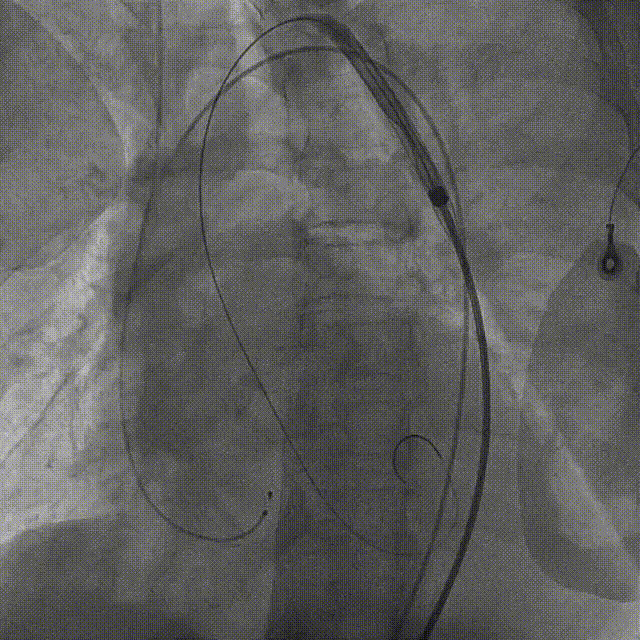

导丝顺利跨瓣

输送器柔顺过弓、跨瓣

瓣膜开始零位定位

瓣膜逐步释放到工作位

工作位造影位置良好

瓣膜逐个脱钩

完全释放后造影,膨胀不良,有漏

25mm球囊后扩

后扩后瓣膜形态良好,造影基本无漏